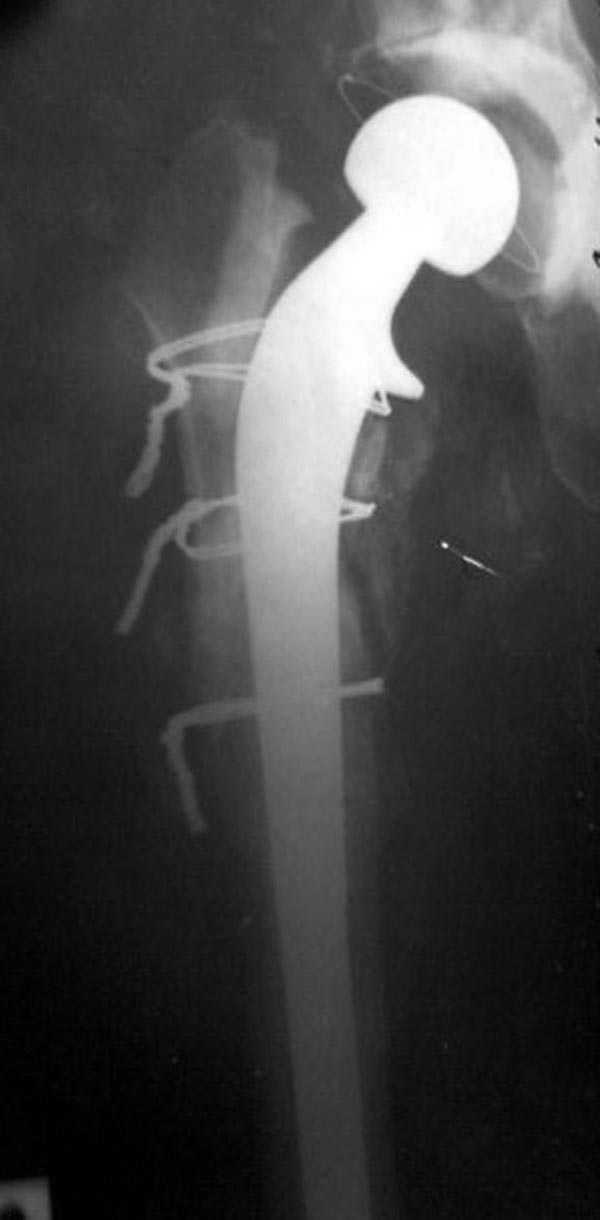

Вот снимки по свежей ситуации, парень 19 лет, длинный оскольчатый перелом бедра от шейки до в-с/3. давно уже ходит на своих ногах.

Представленные Вами рентгенограммы действительно являются примером качественной фиксации спице-стержневым аппаратом. Они, как ни что другое, многое иллюстрируют.

Кроме того, было бы ошибкой ставить знак равенства между нашим и Вашим пациентами. Они не только не похожи, разница между ними просто огромная. Говорю это не для того, чтобы задеть Вас или обидеть. Ни в коем случае. Просто теперь я понимаю, что Ваше мнением строится на простом преломлении Ваших подходов к лечению пациентов со свежими переломами, на ситуацию, абсолютно несопоставимую, подобную нашей.